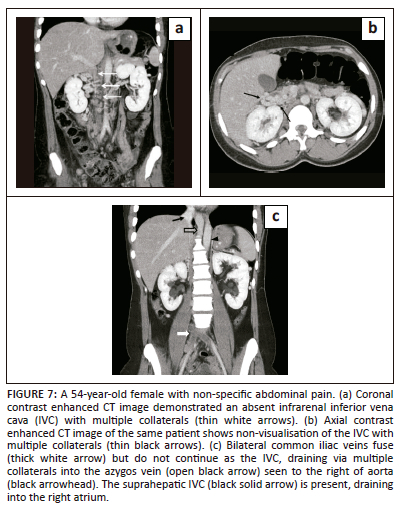

The absence of the inferior vena cava

The entire IVC or only the infrarenal portion of the IVC can be absent. Absence of the entire posthepatic IVC results from failure of development of all three paired venous systems. These are extremely rare. The absence of the infrarenal IVC implies failure of development of the posterior cardinal and supracardinal veins.9 As a single embryonic event cannot explain this abnormality, it is thought that it is not a true embryonic anomaly but the result of perinatal thrombosis and atrophy.1,7,9 Imaging shows the absence of the IVC or a portion of the IVC with prominent venous channels providing collateral flow (Figure 7). These veins are prone to idiopathic deep vein thrombosis and lower extremity venous insufficiency. Prominent lumbar collateral vessels may develop, which can mimic paraspinal masses.9

The common iliac veins can be absent as well. The lower extremity blood drains to the azygos and hemiazygos veins via anterior paravertebral collateral veins. Anterior paravertebral collateral veins receive blood via enlarged ascending lumbar veins, which in turn are formed by the external and internal iliac veins.1